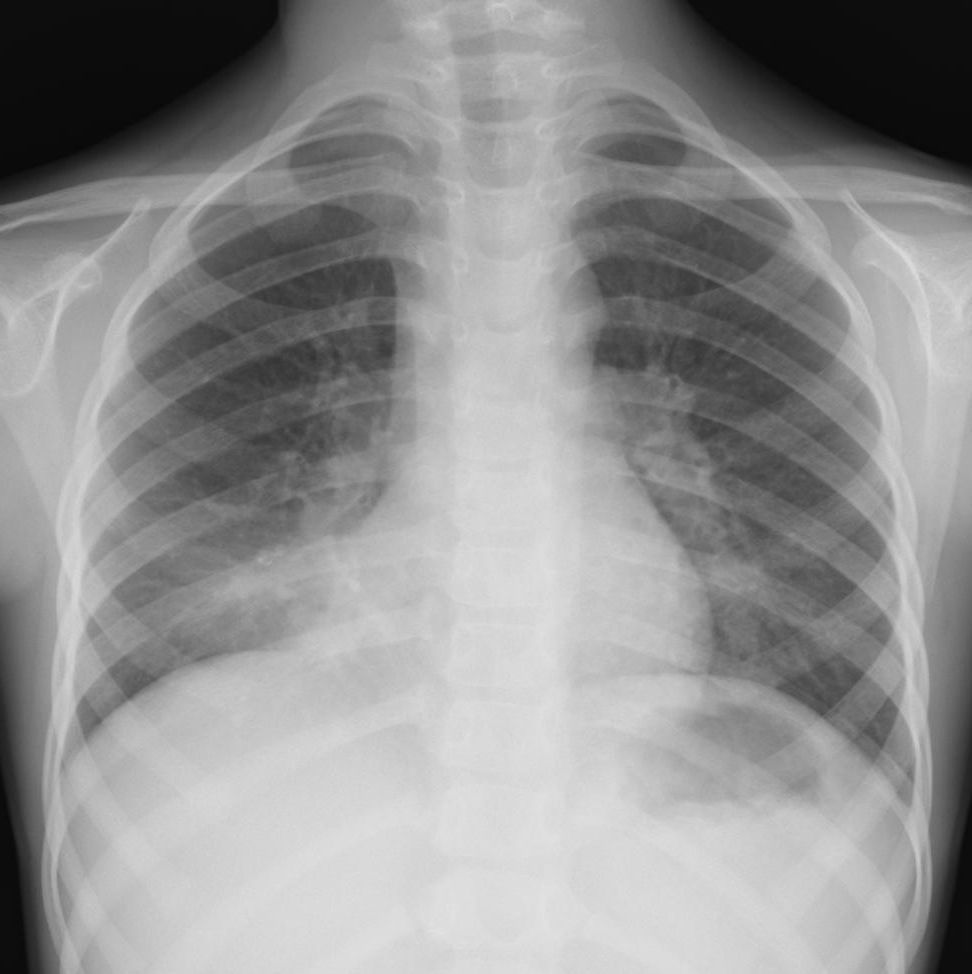

外来でみるクラミジア肺炎

【クラミジア肺炎】